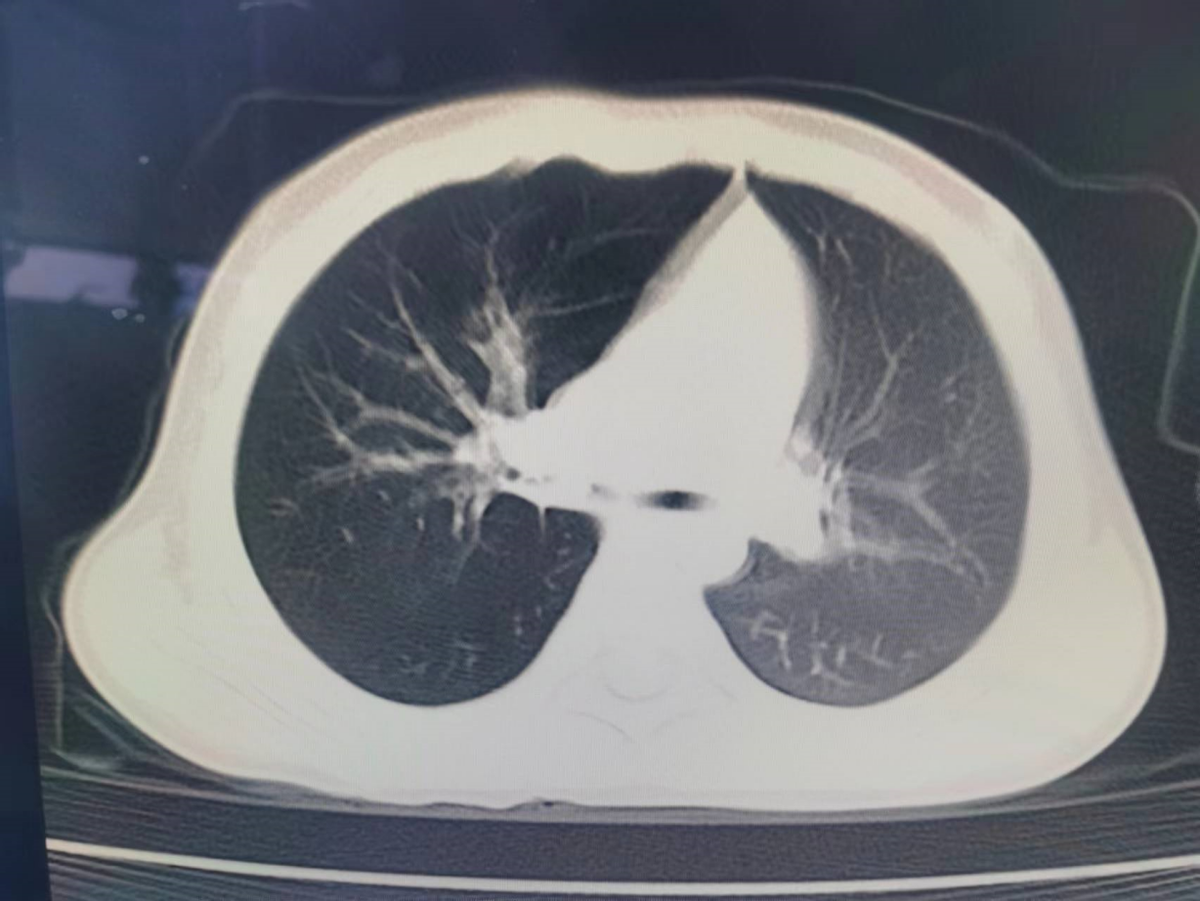

该院儿科呼吸专业团队的医生们,仔细询问患儿发病的整个经过后得知患儿咳嗽突然加重前曾进食过花生,并发生过剧烈呛咳,此后咳嗽一直无缓解,且活动后有气促、喘息,继而出现发热,虽经抗感染、抗炎平喘治疗,无改善。既往 有过3次喘息发作。能过仔细的体格检查发现患儿呼吸增快,右侧呼吸音较左侧减低,双侧闻及多量中细湿罗音和双相喘鸣音。认真分析后疑诊:气管异物伴肺部感染,立即行胸部CT扫描。5月9日10时许,CT扫描报告:右侧主支气管内见一大小约0.5cm结节状影,多系支气管异物,右肺呈肺气肿改变,右肺上叶前段、中叶及下叶散在炎症右肺中叶部分肺不张。真相大白,距患儿入院仅约14小时。

图1 箭头所示,高分辨CT下,右侧主支气内的罪魁祸首无处遁形